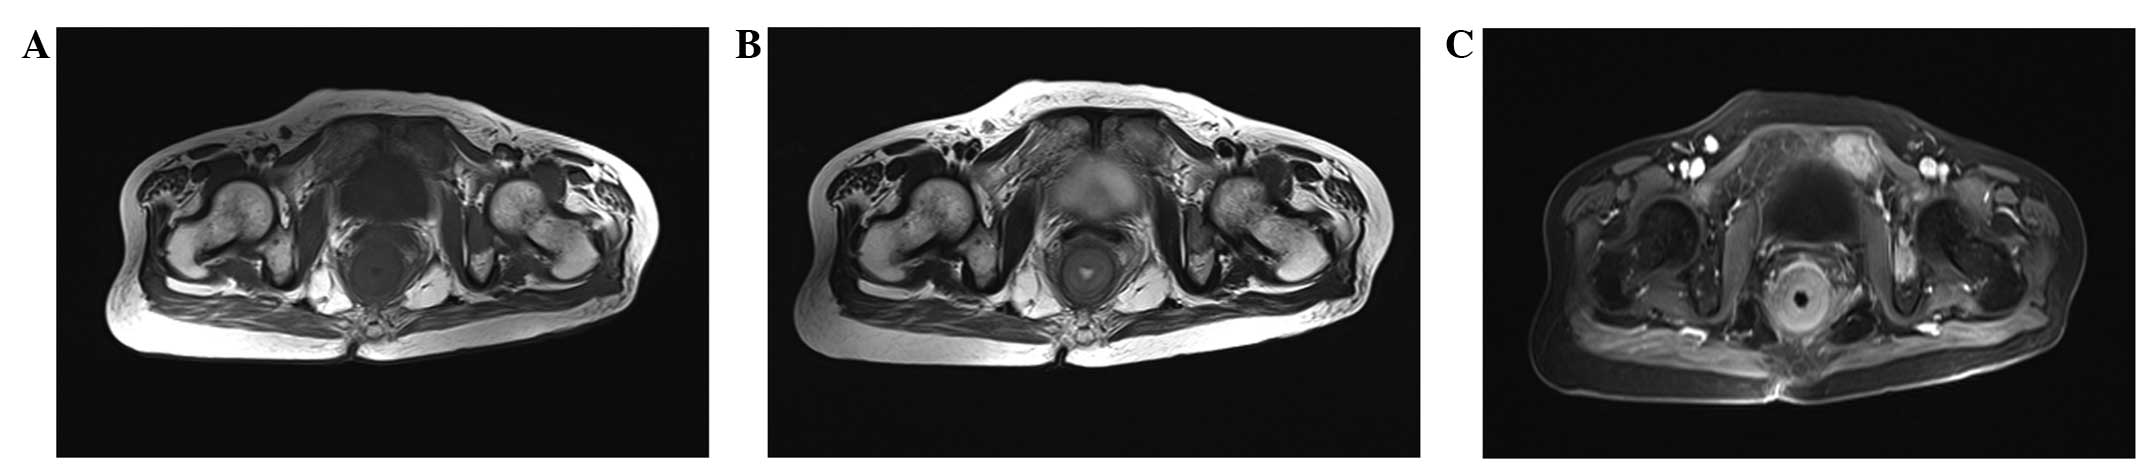

The CT and MRI results are summarized in Table I. All 4 patients exhibited ring-like rectal wall thickening, hypodensity compared with the gluteus muscles on non-enhanced CT images, isointensity on T1WI and hyperintensity on T2WI. Thickening of the left wall of the rectum with patchy low attenuation and the presence of an exophytic mass was observed in 1 patient (patient 4; Fig. 1). Local tumor invasion of the perirectal fat spaces was observed in 4 patients. Tumor invasion of the seminal vesicle was exhibited by 1 patient (patient 1), and tumor invasion of the seminal vesicle and prostate gland was exhibited by 1 patient (patient 4). Heterogeneous attenuation was found on non-enhanced CT images in 3 lesions (patients 1, 2 and 4), and 1 lesion exhibited heterogeneous intensity on non-enhanced MRI (patient 3). All the lesions demonstrated strong enhancement following contrast imaging. Lymphadenopathy was observed in 4 patients, pulmonary metastasis in 2 patients (patients 3 and 4), liver metastasis in 3 patients (patient 2–4) and multiple bone metastases in 1 patient (patient 3; Fig. 2).

Figure 2.

Magnetic resonance images of a 58-year-old woman with small cell carcinoma of the rectum (patient 3). (A) Axial T1WI and (B) axial T2WI demonstrating isointense and hypointense thickening of the rectal wall, respectively, compared with the gluteus muscles. Left pubic bone metastasis was also observed. (C) Axial T1WI fat-suppression demonstrating heterogeneous strong enhancement. WI, weighted images.